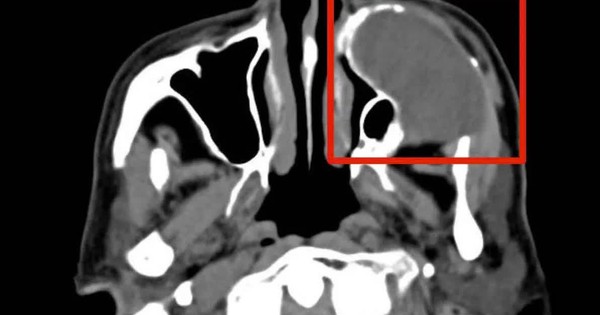

VTV.vn - Chủ quan với u nhầy xoang hàm nhiều năm, người bệnh 76 tuổi nhập viện khi khối u ăn mòn xương, xâm lấn sàn ổ mắt, đe dọa thị lực và gây biến dạng khuôn mặt.